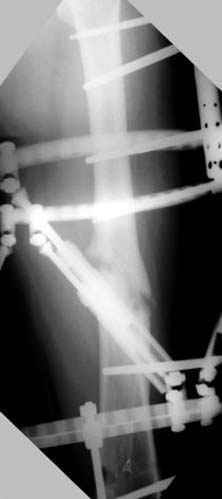

Отправитель: Djoldas Kuldjanov 23 Ноябрь 2004, 18:21

пластическая модель; и коррекция бедра аппаратом Илизарова.

Почему не замена гвоздя с рассверливанием, а аппарат?

Отправитель: Alexander Chelnokov 23 Ноябрь 2004, 21:29

Отправитель: Evgueny Tschekashkin 24 Ноябрь 2004, 21:09

хотя даже если бы и инфекция , то nail exchange с рассверливанием канала - вариант дебрайдмента) Я думаю, что последовательность развития событий:

Узкий к-м канал - тонкий гвоздь- усталостный перелом дистальных винтов - развитие нестабильности и как ее результат остеолиз вокруг гвоздя - деформация анатомической оси бедра. Похоже, что я понял почему аппарат, а не новый гвоздь:-)